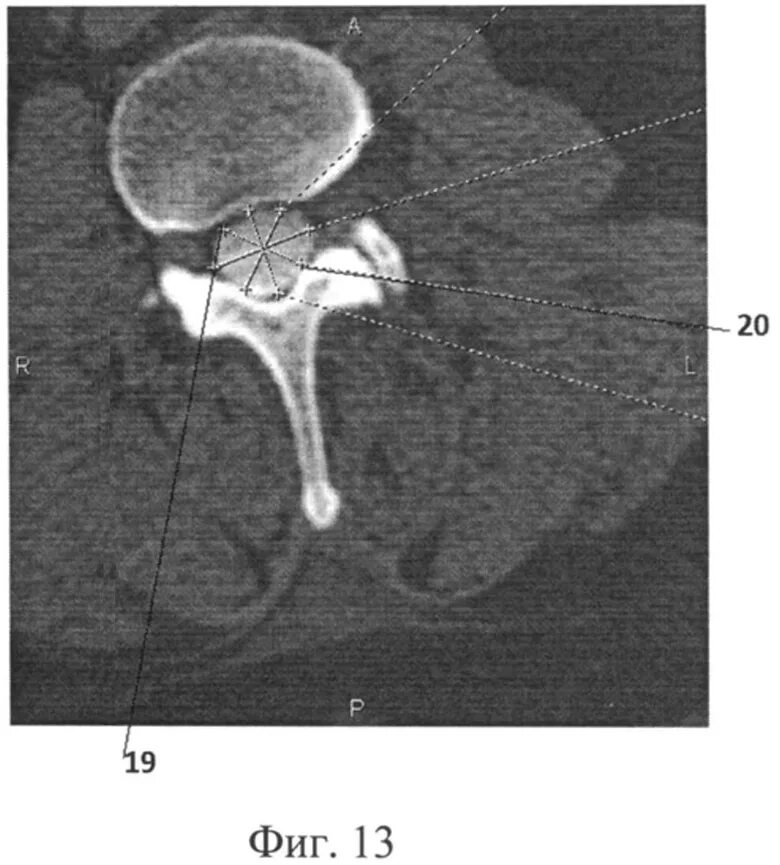

Компрессия дурального мешка что это